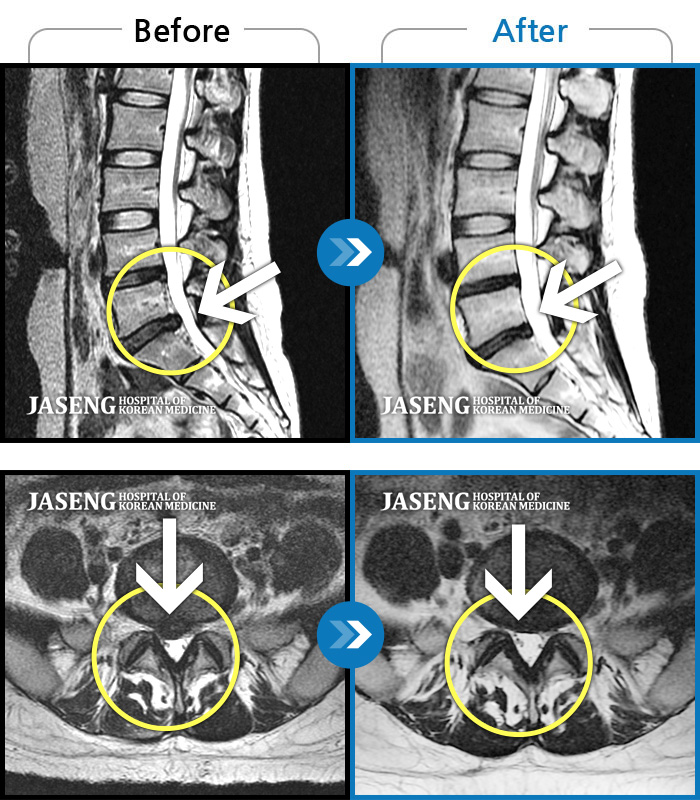

허리디스크

안산 · 조창현 원장

오른쪽 허리 골반 통증이 있으며 엉치 종아리쪽 마비감

촬영시기

2015.09.10 ~ 2016.08.16

2016.08.22

조회수 2,573

우측 다리 통증과 함께 허벅지 뒤로 방사통, 저림

2012.05.31 ~ 2016.06.27

2016.07.25

조회수 6,151